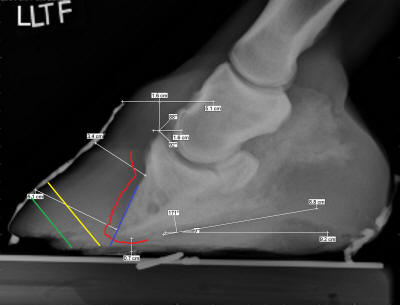

Figure 2

The lamellar wedge –

the area between the now separated hoof wall and P3 varies

dramatically in its texture and integrity. Sometimes it is an

air space or bacteria-infested mush, sometimes it is made of

harder material than the sole, sometimes it is anywhere

in-between those extremes. Occasionally, all or part of the

lamellar wedge is covered over by old sole material which has

been distorted forward of proper support by P3. But the callused

outer periphery of the sole – the tough “extension” of P3 (green

shading) is generally still in the same spot relative to P3.

Using radiographs, or often you can simply see the difference

between the textures and colors of the true sole and the

lamellar wedge, try to locate the border between the true sole

and the lamellar wedge material. If you can find it,

biomechanically, this should be the breakover point, with the

roll beginning 1/4" outside that perimeter (blue lines) to

protect the corium. Assuming the sole is of adequate thickness

(over 1/2"- or 12mm-thick), the wall and lamellar wedge should

be trimmed from this point with the nipper or rasp held on the

angle of a normally rolled wall (red line in Figure 2).